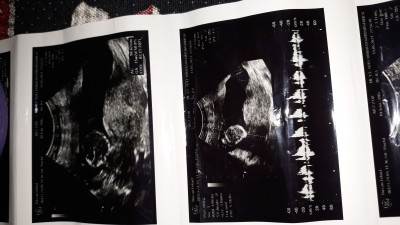

Benim iki kızım var hamileyim doktor gittim 4 aylık dedi ve kız dedi yanilma payı olurmu anlıyan varmi

image